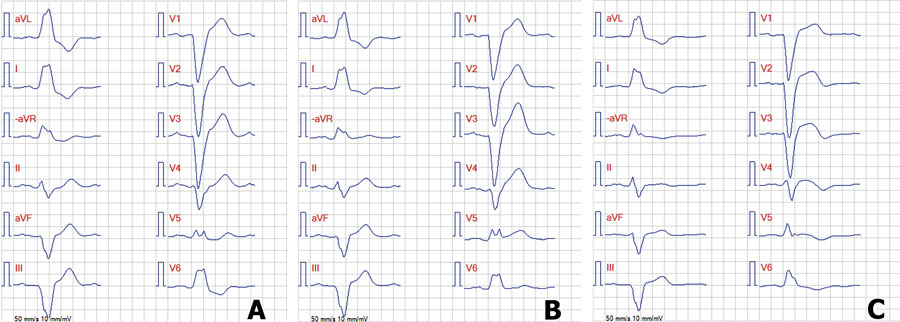

Figur 3. Fallbeskrivning 2.

A. EKG före insjuknandet. EKG visar bredd­ökade QRS-komplex (> 120 ms), djup och bred S-våg i V1 och bred R-våg i V6, som vid vänstergrenblock.

B. EKG taget i ambulansen efter hjärtstillestånd. I V1–V4 har ST-sänkning i J-punkten tillkommit. Dessutom ses ST-höjningar i ­­–aVR, II, aVF och III.